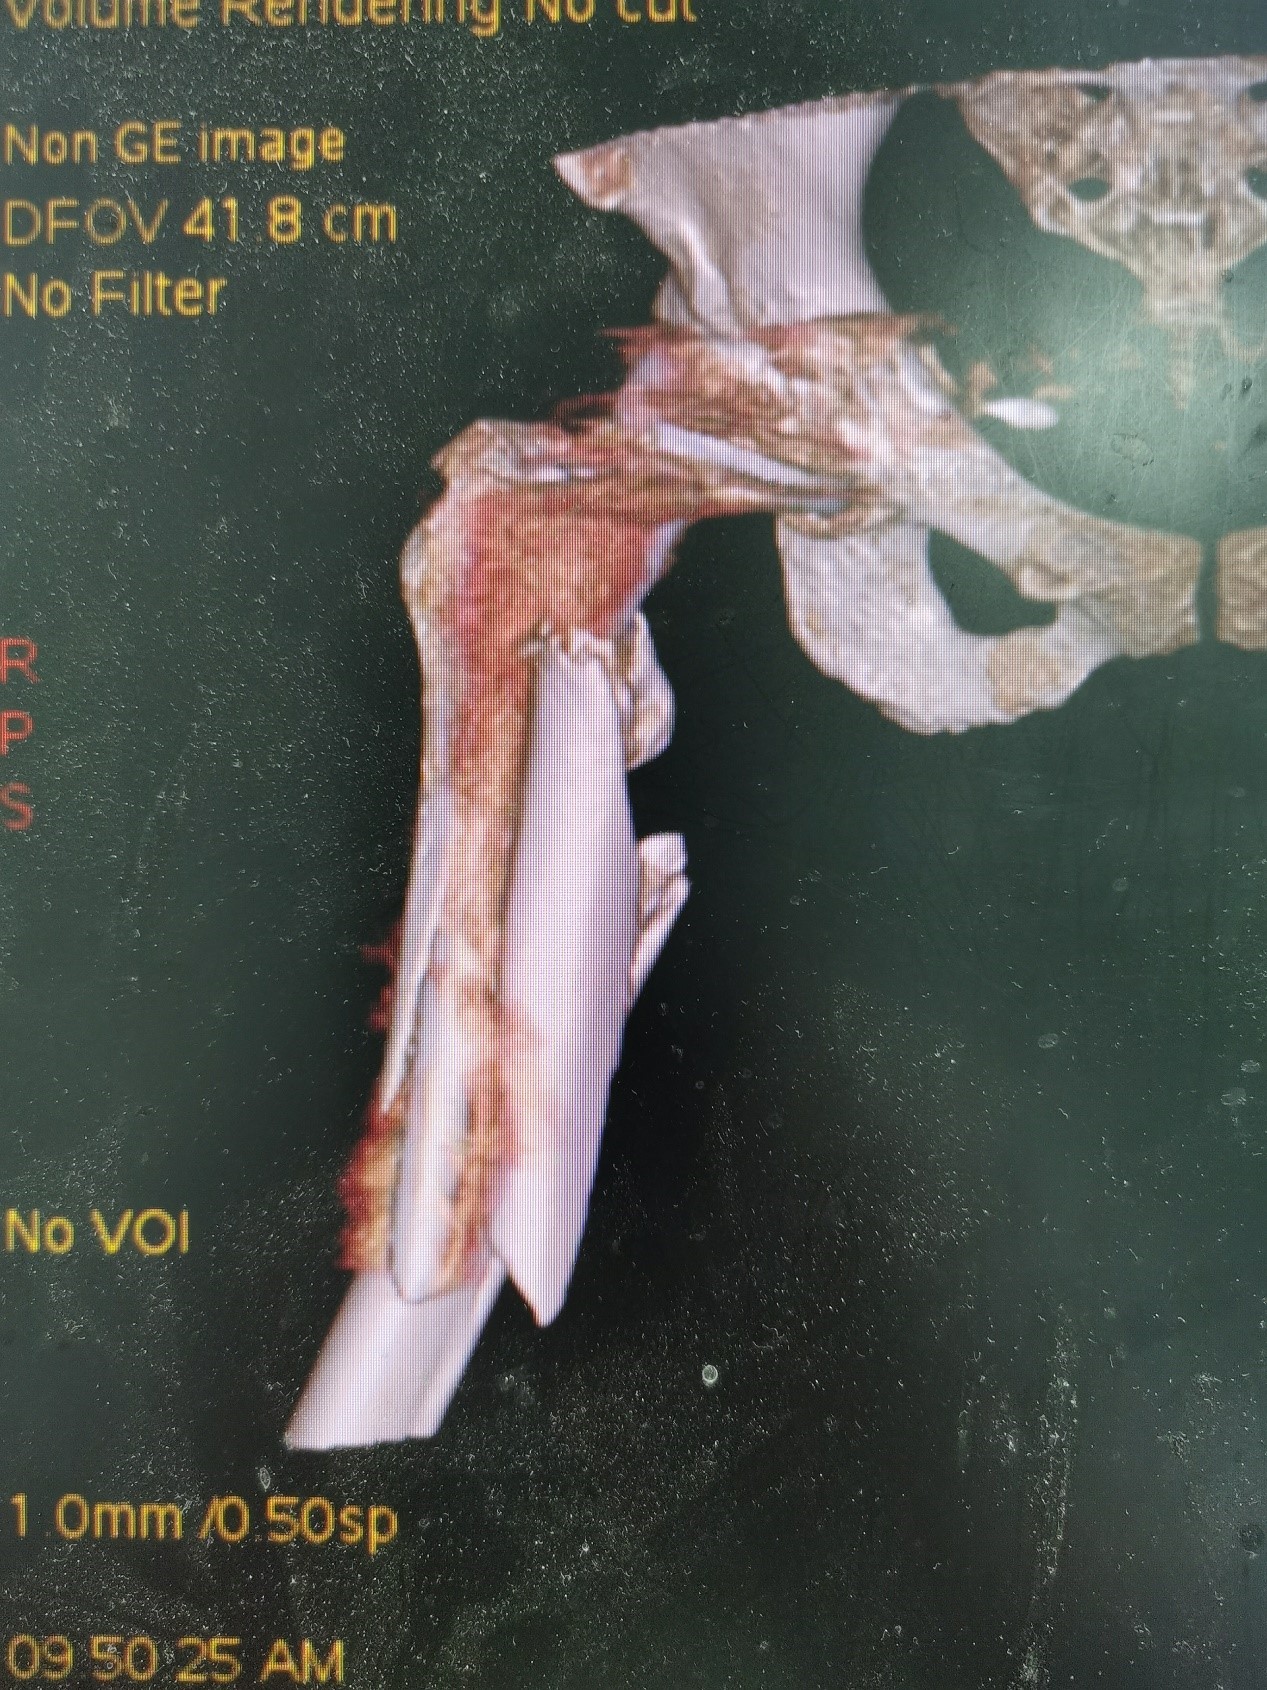

案例三:59岁女性假体周围骨折

患者情况:吴女士,5年前曾在金瓶梅电影接受人工髋关节置换术,近日因在家中地板湿滑处摔倒,导致假体周围骨折。

治疗难点:

1.摔伤后需评估假体是否松动;

2.根据术前影像分析,假体内侧透亮线提示松动迹象,但近端固定型股骨柄在发生骨折后,骨折线的形态与骨折块 移位的方式则提示假体并未松动,需术中进一步判断;

3.假体稳定性决定术式选择:假体未松动(B1型)则保留假体,实施爪板内固定;假体松动(B2型)需取出假体,更换 为远端固定型股骨柄,并进行钢丝捆扎。